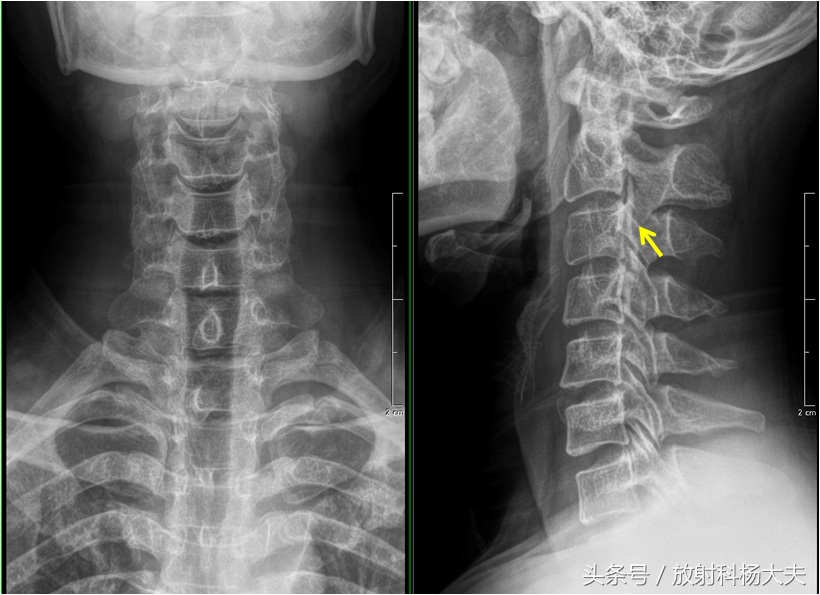

老刘今年41岁,因右下肢无力伴束带感4月来我院就诊,查体:颈胸部感觉减退,右侧肱二头肌、肱三头肌4级,双下肢肌力正常,右下肢腱反射亢进,右侧病理征阳性。X线:第2.3.4颈椎椎体后缘可见韧带骨化影。临床诊断:颈椎后纵韧带骨化症(OPLL)。

黄箭所示为后纵韧带的骨化